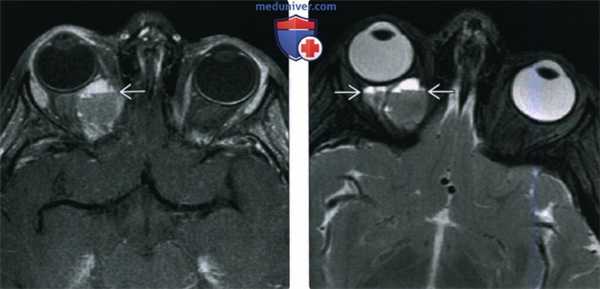

(Слева) При КТ с КУ в аксиальной проекции в правой глазнице в жировой клетчатке внутри мышечного конуса определяется овоидное контрастное объемное образование с четкими контурами, прилегающее к зрительному нерву и наружной прямой мышце.

(Справа) При МРТ Т1ВИ FS с КУ в аксиальной проекции наблюдается интенсивное контрастирование интраконального объемного образования. Образование имеет относительно небольшие размеры, оказывает незначительный эффект объемный эффект и не имеет агрессивных признаков. Такие образования зачастую существуют бессимптомно или вызывают постепенные изменения, не замечаемые пациентом.

(Слева) При КТ с КУ в корональной проекции внутри мышечного конуса определяется объемное образование; наблюдается раннее «лоскутное» контрастирование, что с высокой вероятностью указывает на кавернозную мальформацию глазницы. Хотя образование простирается к периферии глазницы, его центр лежит внутри мышечного конуса.

(Справа) При STIR MPT внутри мышечного конуса определяется крупная кавернозная мальформация. Образование дает интенсивный сигнал, аналогичный сигналу спинномозговой жидкости, окружающей смещенный зрительный нерв.

(Слева) При MPT Т2ВИ FS в аксиальной проекции в правой глазнице определяется крупное гиперинтенсивное несколько дольчатое объемное образование, заполняющее верхушку глазницы. Это медленно растущее образование вызвало расширение верхней глазничной щели.

(Справа) При МРТ Т1ВИ FS в аксиальной проекции наблюдается неполное, но интенсивное контрастирование крупной кавернозной мальформации глазницы, простирающейся в верхушку глазницы. Неконтрастируемые участки, вероятно, будут заполнены контрастом на поздних томограммах.